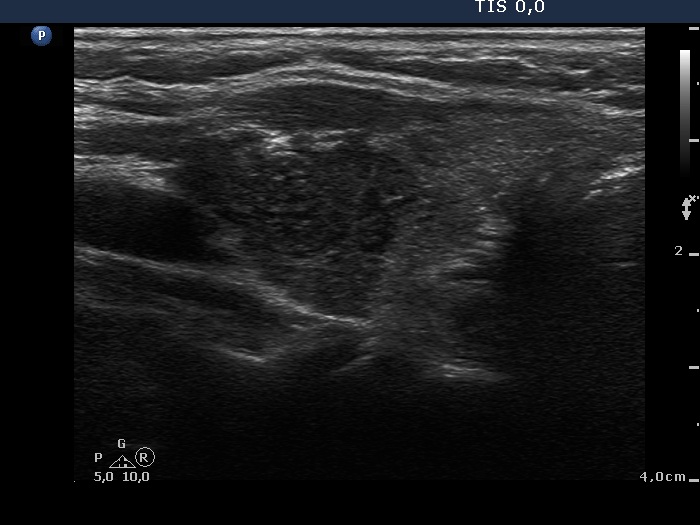

Discrete lesion or nodule in Hashimoto's thyroiditis - case 6 (8) (ultrasonographic picture 7)

Left lobe, another longitudinal scan. The upper part of the lobe is hypoechogenic and in contrast with a true nodule, the lower border is not curved but linear.